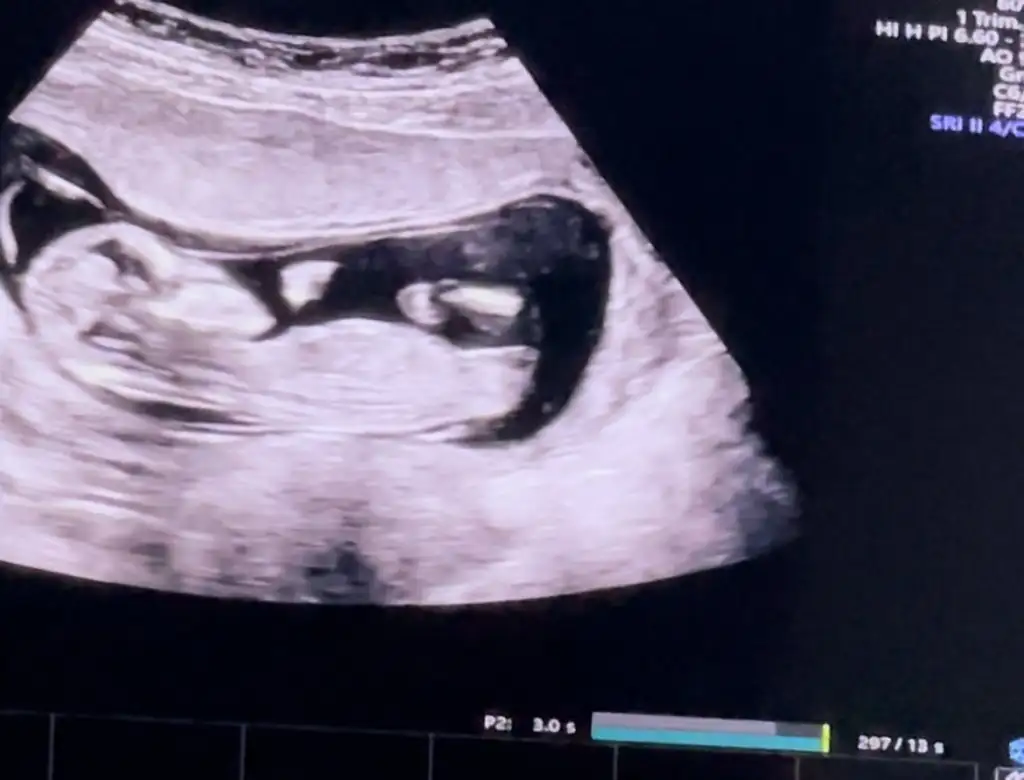

Kız mi dediiiiiiKızlar 12.haftada %90 oranla kız denilmesi ne kadar güvenilir acaba? Bu kadar yüksek oranla kız denilip kızı olanlar yazabilir mi? Ve ya tam tersi olanlar var mı?

Ay canım yazacaktım sanada… ama okuduğum şeylerden sonra biraz korkuyorum sevinmeyeKız mi dediiiiii![]()

O gösterdi ama ben göremedim ya hiç anlamıyorumPeki bacak arasını size göstermişmiydi doktor? Çok teşekkür ederim![]()

Yaaa çok sevindim olsuunn bir umutAy canım yazacaktım sanada… ama okuduğum şeylerden sonra biraz korkuyorum sevinmeyedoktor kendinden emindi… bacak arası boş dedi.. yinede 1 hafta sonra tekrar gel bakalım dedi… sen ne yaptın gittin mi? Ben normalde şimdi gitmeyecektim ama dayanamadım

durum nedir canım gittin mi doktora bir daha :)Kızlar 12.haftada %90 oranla kız denilmesi ne kadar güvenilir acaba? Bu kadar yüksek oranla kız denilip kızı olanlar yazabilir mi? Ve ya tam tersi olanlar var mı?

Canım 13.haftada da kız dedi bana… yani kesin konuşuyor… sizce bukadar kesin konuşuyorsa gerçekten kız mıdır? Nubu da paralel, bacak arasıda boş…B